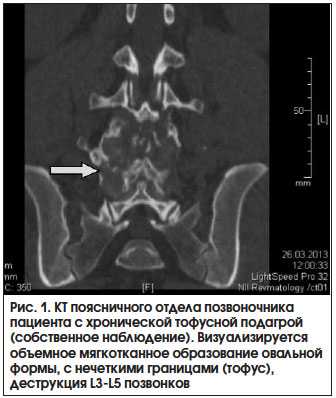

Основное значение для визуализации мягкотканных тофусных масс, прежде всего при их атипичном расположении, имеет МРТ. Наиболее информативными являются режимы Т1 и Т2. В режиме Т1 тофусы выглядят как однородные области с сигналом промежуточной или низкой интенсивности, в режиме Т2 изображения тофусов также характеризуются различной интенсивностью сигнала, которая может быть как гомогенно высокой, так и низкой. Причина, по которой интенсивность сигнала варьируется, может меняться в зависимости от содержания жидкости в тофусе: в случае острого воспалительного процесса, при значительном количестве жидкостного содержимого в формирующемся, воспаленном тофусе отмечается высокая интенсивность сигнала, а при малом количестве жидкости и большом числе кристаллов моноурата натрия, кальцификации тофуса, развитии фиброза, в результате хронического воспаления, обусловленного кристаллами моноурата натрия, или при отложении гемосидерина - низкая [16, 33, 34]. На рисунке 2 представлена МРТ пациента с подагрой.